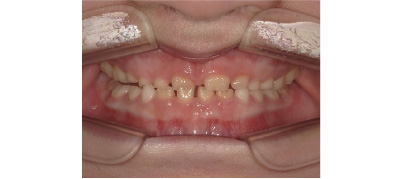

初めて永久歯が生えてくるのは、下前歯からが通常ですが、よく乳歯が抜けずにその内側(舌側)から永久歯が生えてくることがあります。まだ乳歯が抜けていないので驚いてしまうかと思いますが、ほとんどの場合そのまま様子を見ていただいてOKです。

乳歯が抜けると、内側にある永久歯は舌によって外側へ押されているため徐々に本来の位置に動いていきます。永久歯が生えてきて1ヶ月経っても乳歯がグラグラしてこない。食事をすると痛みがある場合はレントゲンを撮って乳歯の根の状態を確認し抜歯となる場合もありますが、ほとんどが様子を見て自然に抜けるのを待つことが多いです。